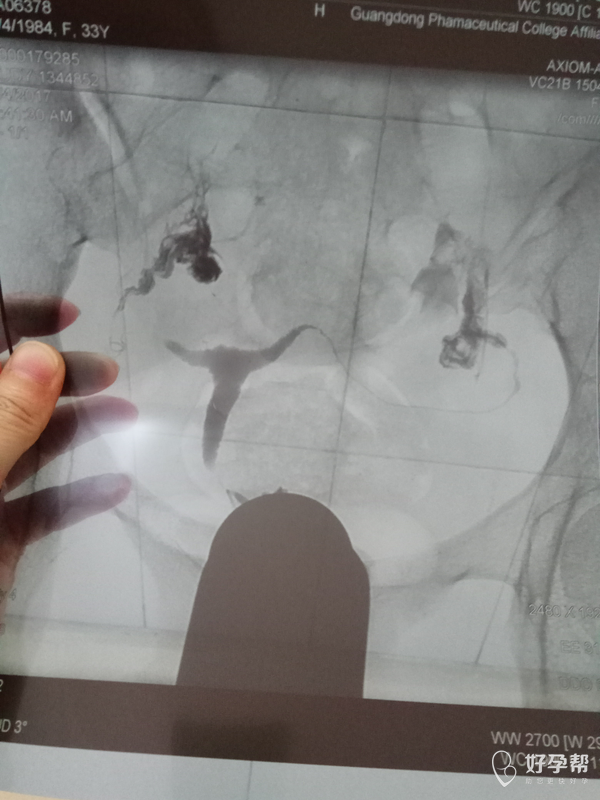

医生帮我看看造影照片,

这是碘油造影吧,双侧输卵管都是通畅的,建议积极试孕,祝好孕